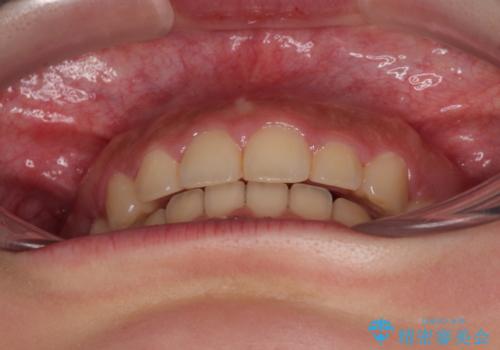

- 飛び出した上顎前歯と、閉じにくい唇、口元の突出した印象の横顔を気にして来院された患者様です。

事前の予想通り、長期間を要する治療となりましたが、横顔の印象が劇的に変化し、患者様には大変満足していただきました。